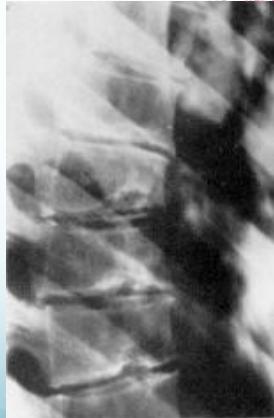

Radiographic Findings:

- Irregular ossification of vertebral body epiphysis

- Schmorl’s nodes -Central herniation of disc material into the body

- Wedging of vertebrae

X-ray Findings

- Schmorl’s nodes (central disc herniation)

- Vertebral wedging